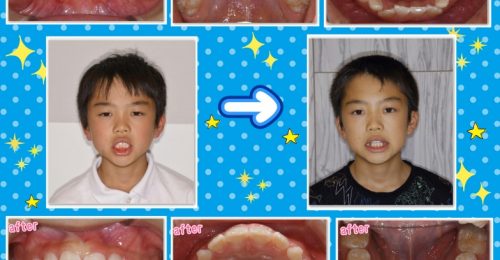

キレイにならびました♪ 頑張りましたね^^ ☆治療内容 インビザラインファースト による小児矯正治療 ☆治療期間 1年半 ☆治療費用 495,000円(税込) ☆リスク 歯を動かすためには1日22時間以上の装着が必要です ※写真掲載許可あり ****************************** 【診療時間】 …